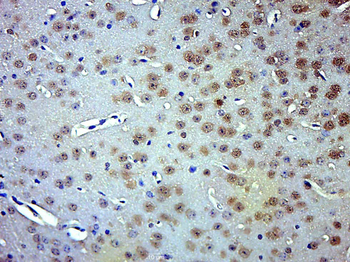

Phospho-Smad3 (Ser423 + Ser425) Rabbit Polyclonal Antibody [orb6983]

FC, IF, IHC-Fr, IHC-P, WB

Bovine, Canine, Equine, Gallus

Human, Mouse, Porcine, Rat

Rabbit

Polyclonal

Unconjugated

100 μl, 200 μl, 50 μlPhospho-SMAD5 (Ser463 + Ser465) Recombinant Rabbit Monoclonal Antibody [orb559123]